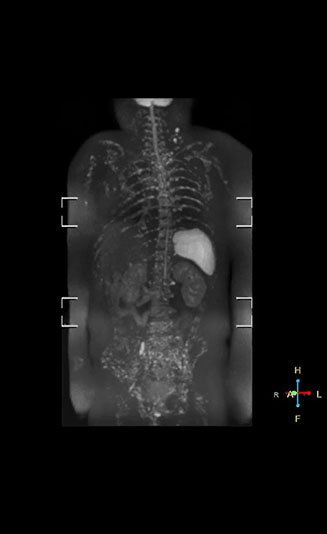

“When we limited the scan coverage to the area from neck to femur, we could fit more clinical information in approximately the same scan time. So, we added coronal mDIXON, sagittal T1-weighted, and sagittal STIR sequences to our examination, instead of performing only axial DWIBS and coronal single-shot TSE scans.” The single shot T2-weighted TSE images are used for morphology and compared to DWIBS images to identify T2 shine-through. Sagittal STIR images are used in patients with inflammation or bone metastasis.

“Switching to coronal DWIBS – rather than axial – further shortens scan time,” says Mr. Naka. “Important is that a dS SENSE factor of 5 shortens exam time while high image quality can be maintained, thanks to Ingenia’s dStream architecture.” He adds that the coronal orientation also avoids artifacts that are specific to combining axial images.

“When we use a coronal DWIBS acquisition, we can perform a full whole body examination, including other required sequences, within 30 minutes,” he says.

“mDIXON FFE allows us to quickly get information we need to assess the presence of fat. That gives us more information when we need to diagnose bone lesions, and when we are asked to judge fat-containing lesions such as hepatocellular or renal carcinoma,” Dr. Nobusawa says. “The mDIXON fat images can help us to differentiate fatty bone marrow from bone lesions. This is especially useful in elderly people, who tend to have fattier bone marrow. The water images provide a high signal-to-noise ratio in the intestinal canal, which is valuable for visualizing lesions in the colon,” he says.

Kawasaki Sawai Hospital’s whole body protocol also includes an mDIXON FFE sequence. Because mDIXON provides images for four contrast types – water only, fat only, in-phase and out-of-phase – from a single acquisition, it is useful in many ways.